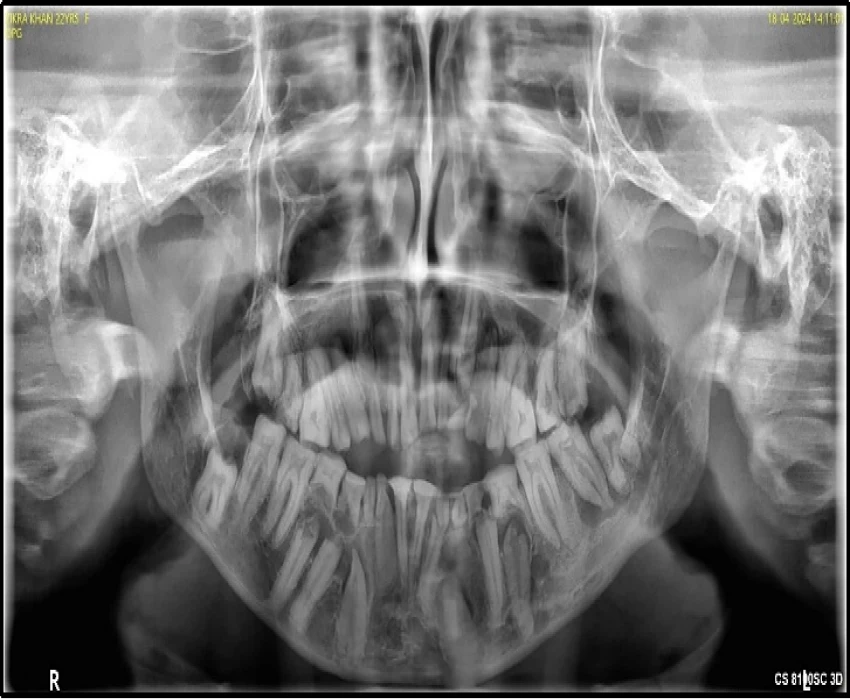

The patient came to the Department of Oral Medicine and complains of delayed eruption in lower front region of the jaw since 16 yr and irregular size and shape of the teeth in maxillary and mandibular region of the jaw since eruption of the teeth.

On intra-oral examination generalized loss of cervico-occlusion height and colour of the teeth appeared opalescent and brown in colour.

On the basis of history, clinical examination, and radiographic investigation final diagnosis was given as Amelogenesis imperfecta- Hypoplastic Type.

In patients with hypoplastic amelogenesis imperfecta, the basic alteration centers on inadequate deposition of enamel matrix. In the generalized pattern, pinpoint-to-pinhead–sized pits are scattered across the surface of the teeth and do not correlate with a pattern of environmental damage. The buccal surfaces of the teeth are affected more severely. Both dentitions, or only the primary teeth, may be affected. All of the teeth may be altered, or only scattered teeth may be affected.